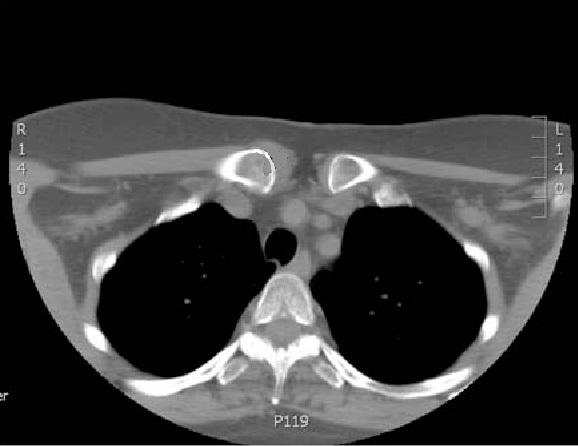

Aspect d'élargissement et

épaississement du cartilage au niveau de articulation

sternocostale gauche et oedème de la moelle

osseuse dans sous-chondral . Image radiologique TDM

coupe axial d'une syndrome Tierzt gauche du thorax